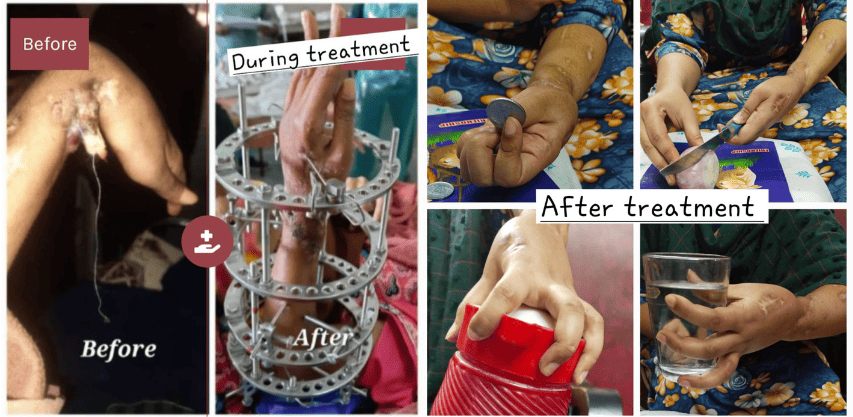

Ilizarov for malunited fracture with bad skin condition

Ilizarov for Upper Limb

Infected nonunion forearm before and after the treatment